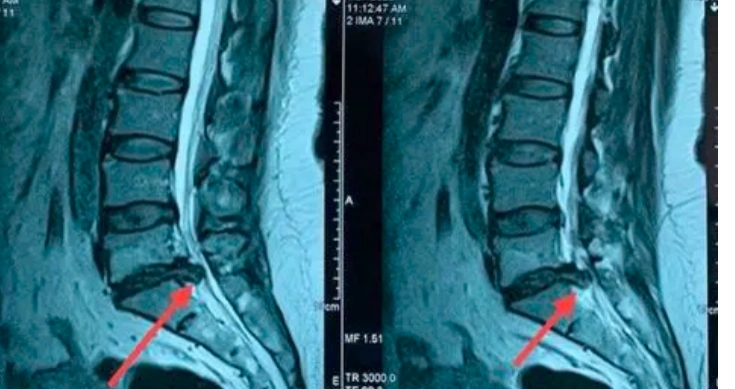

腰椎间盘膨出伴后突出

腰椎间盘膨出突出脱出这些区别一目了然